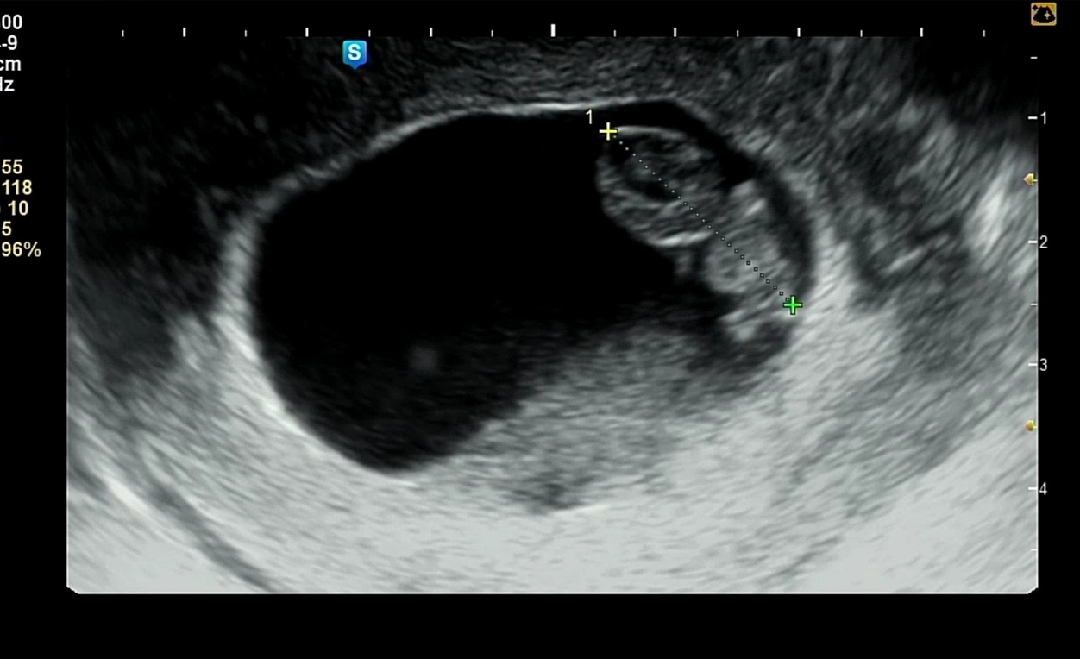

8주차 젤리곰 보고왔어요

우리 찰떡이 앞으로도 잘크자🥰